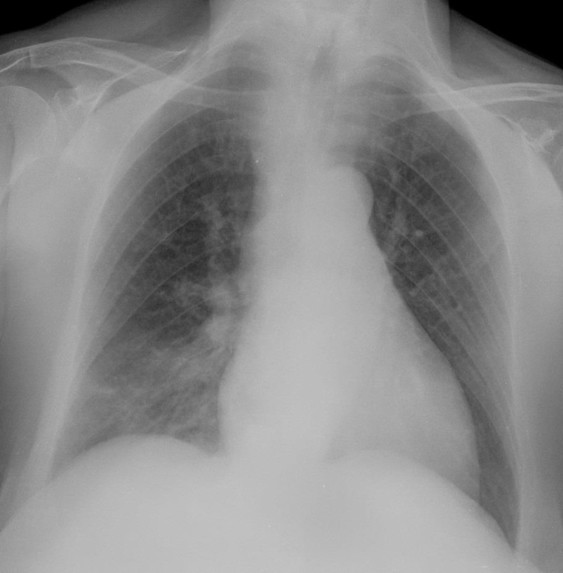

RoboDoc is a messenger bot where people could chat with it and get their symptoms analyzed using messages. Based on symptoms sent by the user it analysis and most accurate diseases are diagnosed. At present we have added 21 common diseases we will be expanding it to 87 diseases our main objective was to lessen the panic caused by the coronavirus pandemic. We have added analysis of Frontal chest x-ray for covid19 and analysis of mammography for breast cancer detection.

For the COVID19 detection model using X-rays, we used Kaggle and Github dataset accounting for total of 1300 COVID19 and 1200 normal chest x-rays. For breast cancer, we used the Kaggle dataset. For symptoms and disease, we used a CSV file for NLP training.

We are using wit.ai for Natural Language Processing and based on symptoms mentioned by users we are predicting the disease and for detection of covid19 using chest x-ray and breast cancer using mammography we are using tensorflow.js models and javascript